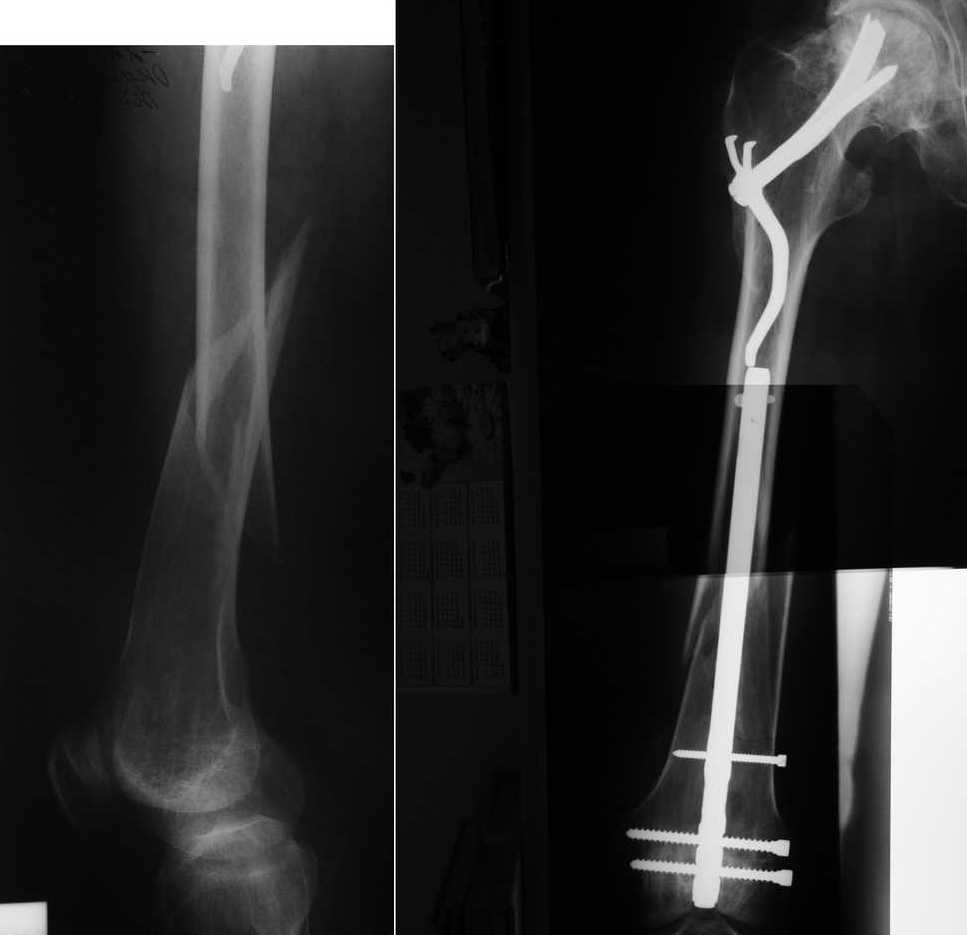

Хотим напомнить о забытом, эффективном методе остеосинтеза медиальных переломов шейки

бедренной кости. Пациенту 55 лет был выполнен остеосинтез медиального перелома шейки

бедренной кости фиксатором Сеппо 15 лет назад. В течение этих лет пациент жил не тужил, пока в

марте сего года не получил перелом диафиза этого же бедра. Мы сочли единственно возможным

применение в данной ситуации метода остеосинтеза штифтом с ретроградным введением. С

удовольствием выслушаем ваши мнения. Возможно у кого-то ещё есть опыт применения

фиксаторов Сеппо.